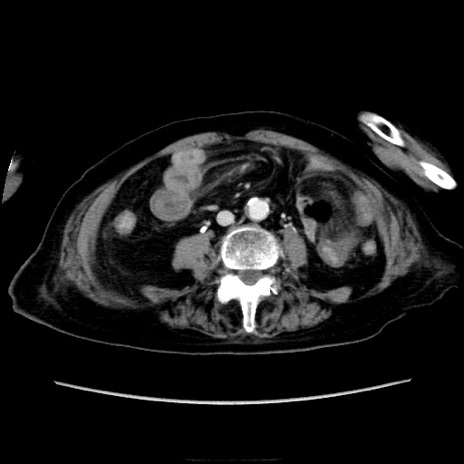

他院CT

冠状断像

【症例】90歳代女性

【主訴】腹痛・嘔吐

【現病歴】 食欲低下、嘔吐があり昨日他院受診。肺炎と診断され入院となる。入院後より腹部全体に圧痛あり。胃管留置され経過みていたが、症状持続するため、

当院転院となる。

【既往歴】胸椎圧迫骨折、胆石症

【身体所見】腹部:中央に激痛あり、圧痛あり、反跳痛不明

【データ】WBC 17100、CRP 18.82